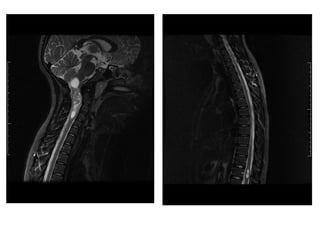

●2) N.C.S.C, 12ª ●Data da consulta: 01-10 -2013 ●Cefaléiahá 3 meses + perda do equilibrio+ sem vômitos ●Oftalmo–erro de refração -> alteração de campo visual ●Neuro-> TC de crânio há 1 mês -> RNM após 15 dias ●RNM ( 25-09) : lesão infiltrativade tronco cerebral , estendendo –se do mesencéfalo à medula cervical ao nível de C1-C2 com hidrocefalia osbtrutiva- glioma ●Exame fisico: Glasgow15, ataxiacerebelar, pares cranianos Ok, força preservada,olhar em sol poente; ●Manchas café-com –leite ●Diagnóstico: Neurofibromatosetipo 1 +gliomade bxgrau óptico –hipotalâmico +gliomade tronco difuso

GLIOMA HIPOTALÂMICO-QUIASMÁTICO ●Sub-grupomaiscomum de gliomade baixo-grau (60%); ●Cças< 5 anos; ●Apresentação clínica: sínd.diencefálica, anormalidades endócrinas e deterioração visual;

3)E.S., 4anos e2meses, Data da consulta:25-06-2013 Ataxialateralizadaà direita +alteração de comportamento =agressividade Sem cefaléiae sem vômitos RNM –formação expansiva em tronco cerebral 12 mmx15 mm Tratamento: Rxt